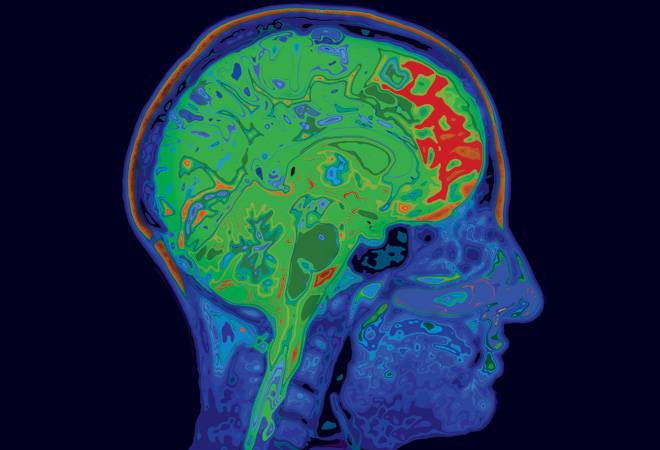

For years now, we have come across bulky MRI (magnetic resonance imaging) machines, those enormous and somewhat intimidating chunks of infrastructure which would often make us panicky. Still astonishing is their ability to capture detailed images of internal organs and soft tissues - something that X-rays and CT scans cannot do - to help with diagnosis. There is just one glitch. The machines have not shed their bulk even in this age of nanotechnology; neither do they fit in an ambulance. But efforts are on to miniaturise them as portability is crucial to widen their reach and enhance their functionality.

A traditional MRI machine creates a strong magnetic field around the human body. This interferes with the fundamental magnets in our body - namely, the spinning electrons and protons lying in the nucleus of every atom of each body cell. The energy from the MRI-generated spinning/oscillating magnetic field creates a brief pulse of radio-frequency (RF) energy, which makes the protons spin perpendicular to the pulse. When the protons release that energy and return to normal, sensors measure the same and turn them into images. Understandably, billions and billions of spins are needed to gather adequate data for diagnostics.

To scale down their MRI device, the researchers put all these MRI capabilities into a scanning tunnelling microscope with a sharp metal tip. The two atoms (iron and titanium) studied for this project were highly magnetic and distinctly visible through the microscope. The team then used the microscope's tip as an MRI scanner and 3D-mapped the image at high resolution.

This extreme miniaturisation of the MRI process is a breakthrough as it enables the study of a single atom with great precision, records the signature structure of the material and also manages to differentiate between two atoms made of different stuff but lying next to each other. The researchers think this new technique could lead to the development of new drugs, new materials and better quantum computing systems. "We can now see something that we couldn't see before," IBM scientist Christopher Lutz told The New York Times. "So our imagination can go to a whole bunch of new ideas that we can test out with this technology."